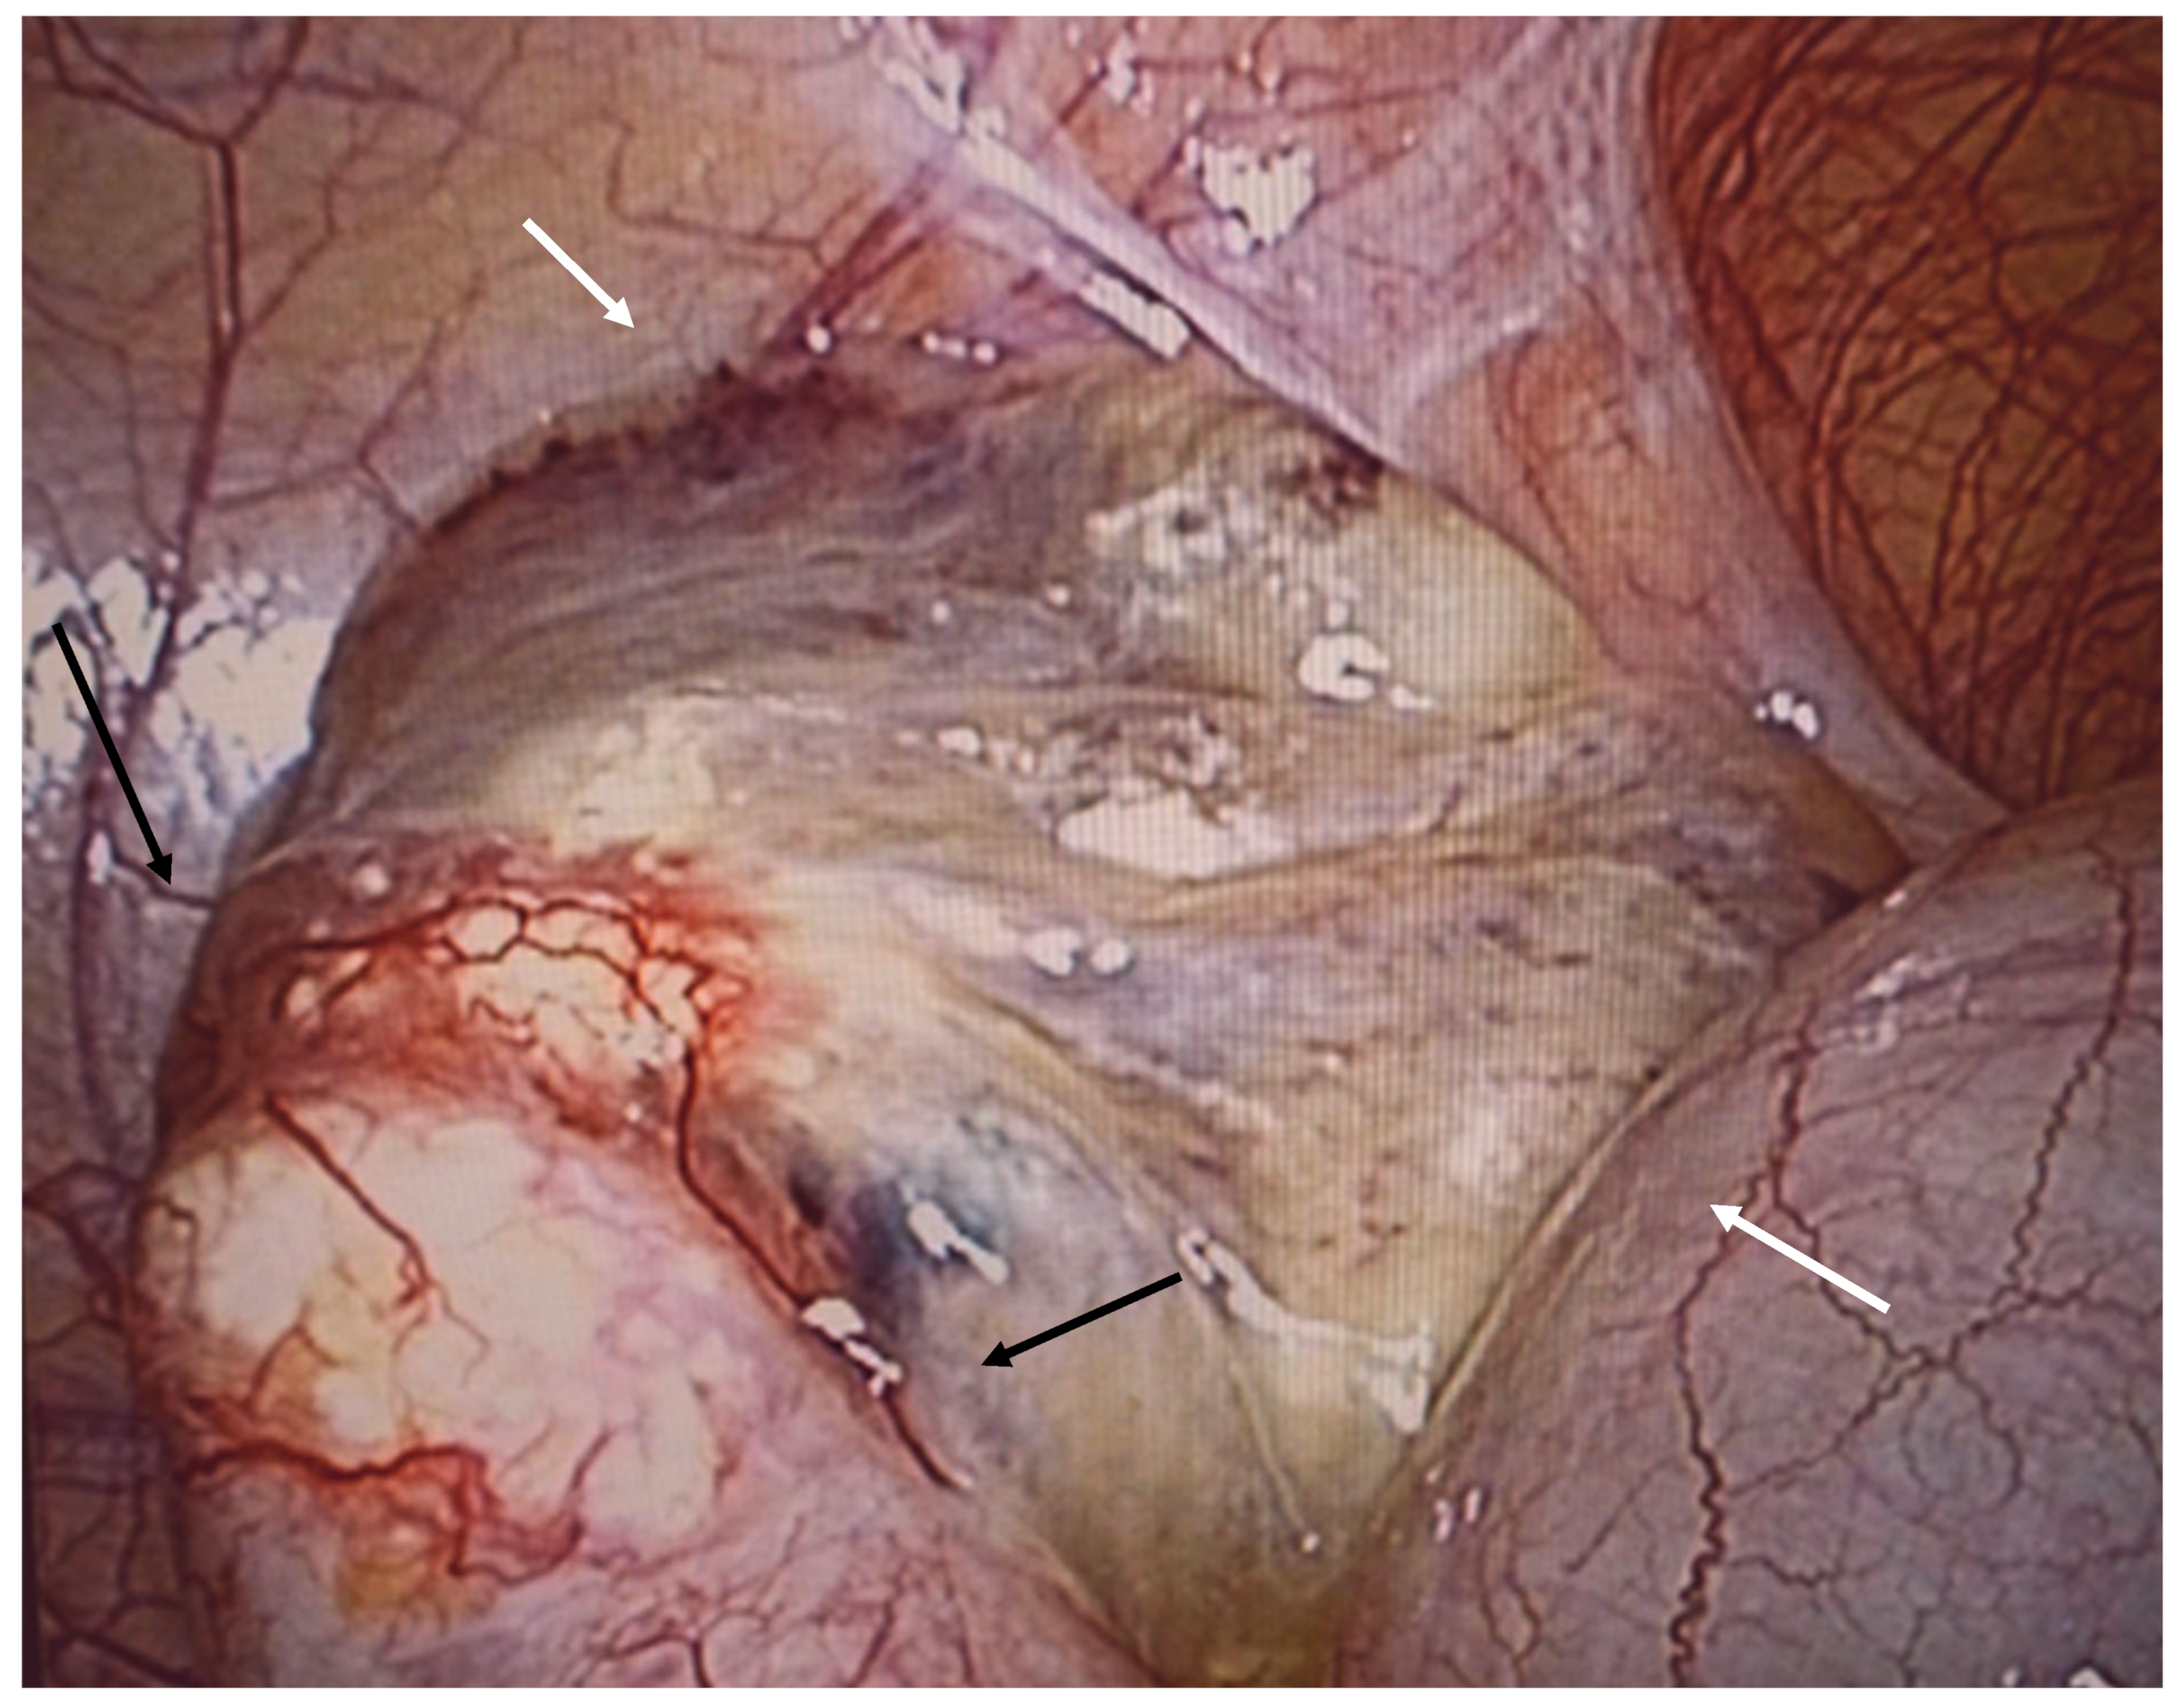

Figure 10. Ruptured mucocele of the appendix in perioperative view. Part of the appendix (black arrow) is embedded in mucus (white arrow), which covers the perforation.

The mucocele ruptures due to increased intra-appendicular pressure, releasing mucus and tumor cells into the peritoneal cavity (Figure 9 and Figure 10). The rupture may be asymptomatic or associated with only mild and nonspecific clinical signs. Typical peritoneal signs and bacterial peritonitis are usually absent because the communication to the lumen of the colon is closed by mucin. Treatment in these cases is called a radical appendectomy, with the resection of the cecal bases, but without a right colectomy. The addition of HIPEC is fully indicated. It is necessary to examine the whole abdomen to exclude the presence of tumors in typical locations, such as the Douglas pouch and the undersurfaces of the diaphragm and the right and left paracolic gutter.